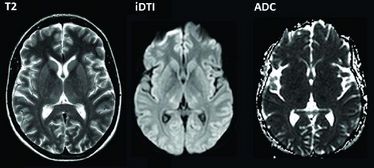

Meuth und seine Kollegen verglichen die MRT-Aufnahmen des Gehirns, die in der Radiologie angefertigt wurden, mit Messungen der Gehirnströme aus der Neurologie: Im Anschluss untersuchten Mitarbeiter des Instituts für Physiologie I sowie der Abteilung für entzündliche Erkrankungen des Nervensystems und Neuroonkologie das Virustoxin in verschiedenen experimentellen Modellen, unter anderem mithilfe von elektrophysiologischen und Zellgewebsanalysen. Allmählich vervollständigte sich das Bild.

Es zeigte sich, dass sieben Patientinnen neurologische Symptome und Gewebeschädigungen im Gehirn aufwiesen. „Das Zellsterben fand sich insbesondere in einem bestimmten Teil des Zwischenhirns, dem Thalamus. Und auch einige der krankhaften Veränderungen des Gehirns wurden offenbar dort ausgelöst.“ Der Ort der Krankheit war damit gefunden. Experimentelle Studien an Ratten lieferten dann den entscheidenden Hinweis darauf, was die gefährliche Schädigung verursacht: „Wir fanden im Thalamus weiblicher Ratten den Rezeptor für das EHEC-Gift Shiga-Toxin 2 in deutlich größerer Menge als in allen anderen Teilen des Gehirns. Zugleich tritt der Rezeptor stärker auf als im Thalamus männlicher Tiere“, erläutert Sven Meuth die zentrale Erkenntnis der Wissenschaftler.